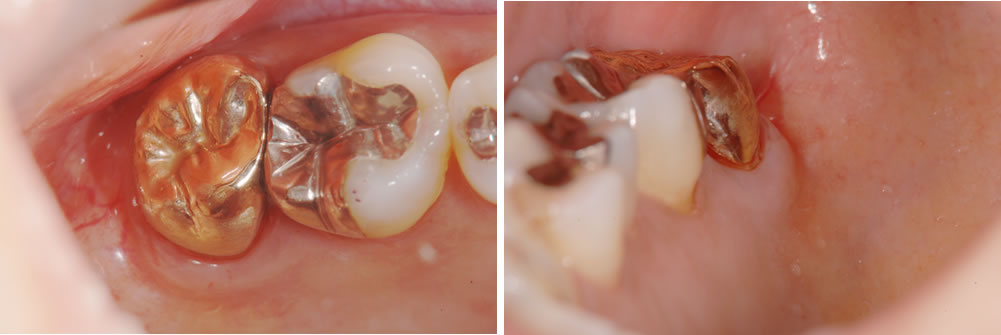

初診時の口腔内

実際にその歯を診てみると、中央に大きな銀の土台が入ってはいるものの、その周囲の歯との境目から歯が裂けている状態でした。こちらの写真からもはっきり確認いただけると思います。

また、歯と歯の間に汚れも多く付着していました。